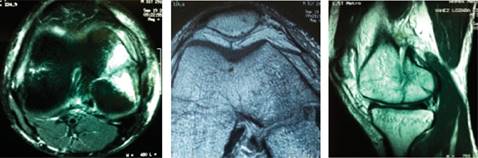

El paciente se presentó con radiografías anteroposterior y lateral de la rodilla derecha fechadas el 12 de Septiembre de 2011, en las que se apreció solución de continuidad de cóndilo femoral medial en sentido coronal, con compromiso articular y desplazamiento de 3 mm (Figura 1). También contó con resonancia magnética fechada el 19 de Septiembre de 2011, que mostró una fractura coronal de la porción posterior del cóndilo femoral medial con desplazamiento de 3 mm en la superficie articular, con probable lesión de ambos meniscos y probable lesión de ligamento cruzado anterior (Figura 2).

Figura 2: Resonancia magnética nuclear de rodilla derecha donde se observa el trazo completo, compromiso intraarticular y desplazamiento del fragmento óseo condilar.